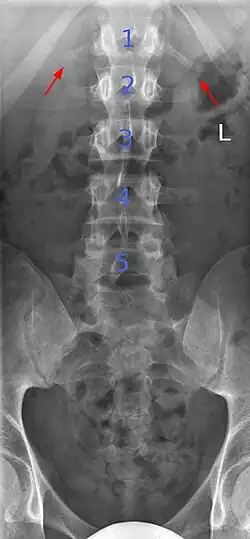

Lumbarization and sacralization

Lumbarization is an anomaly in the spine. It is defined by the nonfusion of the first and second segments of the sacrum. The lumbar spine subsequently appears to have six vertebrae or segments, not five. This sixth lumbar vertebra is known as a transitional vertebra. Conversely the sacrum appears to have only four segments instead of its designated five segments. Lumbosacral transitional vertebrae consist of the process of the last lumbar vertebra fusing with the first sacral segment. [1] While only around 10 percent of adults have a spinal abnormality due to genetics, a sixth lumbar vertebra is one of the more common abnormalities. [2]

Sacralization of the fifth lumbar vertebra (or sacralization) is a congenital anomaly, in which the transverse process of the last lumbar vertebra (L5) fuses to the sacrum on one side or both, or to ilium, or both. These anomalies are observed in about 3.5 percent of people, and it is usually bilateral but can be unilateral or incomplete (ipsilateral or contralateral rudimentary facets) as well. Although sacralization may be a cause of low back pain, it is asymptomatic in many cases (especially bilateral type). Low back pain in these cases most likely occurs due to biomechanics. In sacralization, the L5-S1 intervertebral disc may be thin and narrow. This abnormality is found by X-ray.